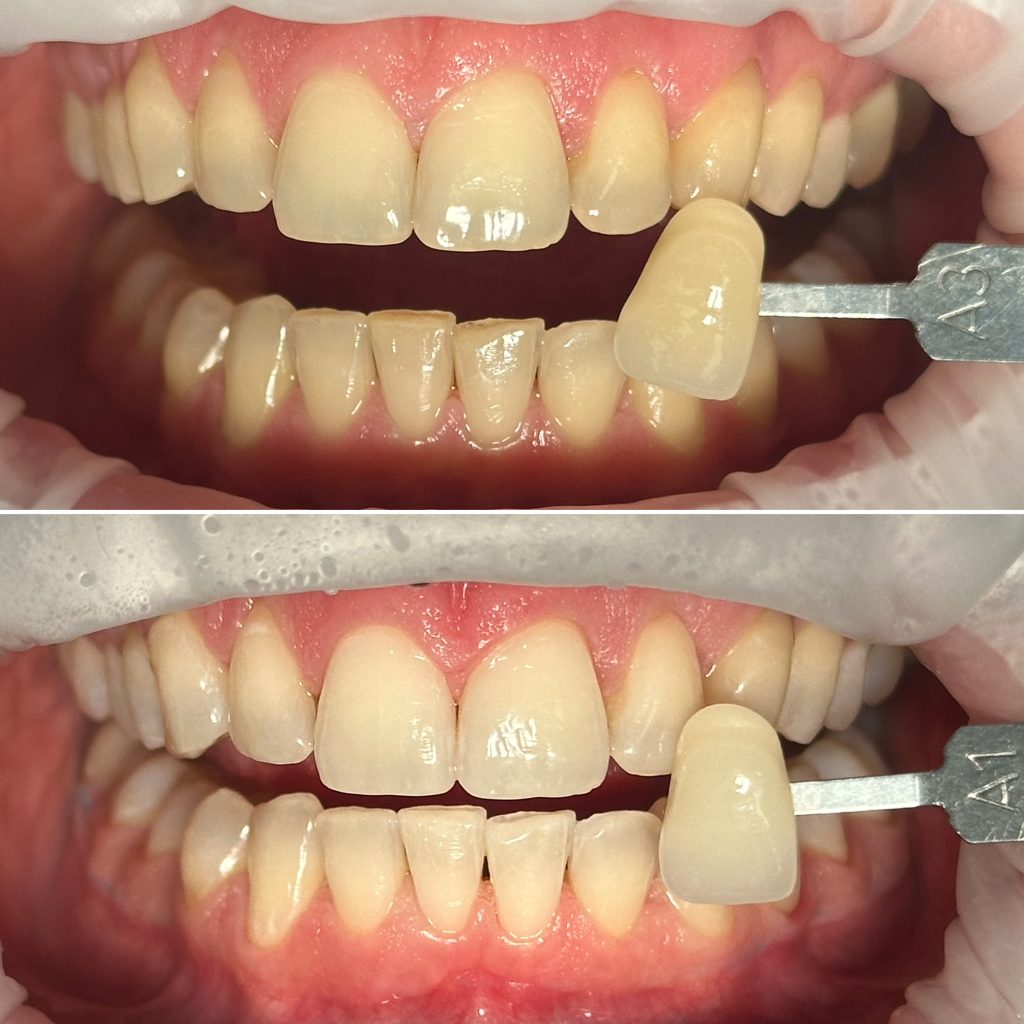

• Профессиональная отбелка зубов системой ZOOM,BEYOND

2024 год – «Отбеливание от «А» до «Я» Александр Кирманов